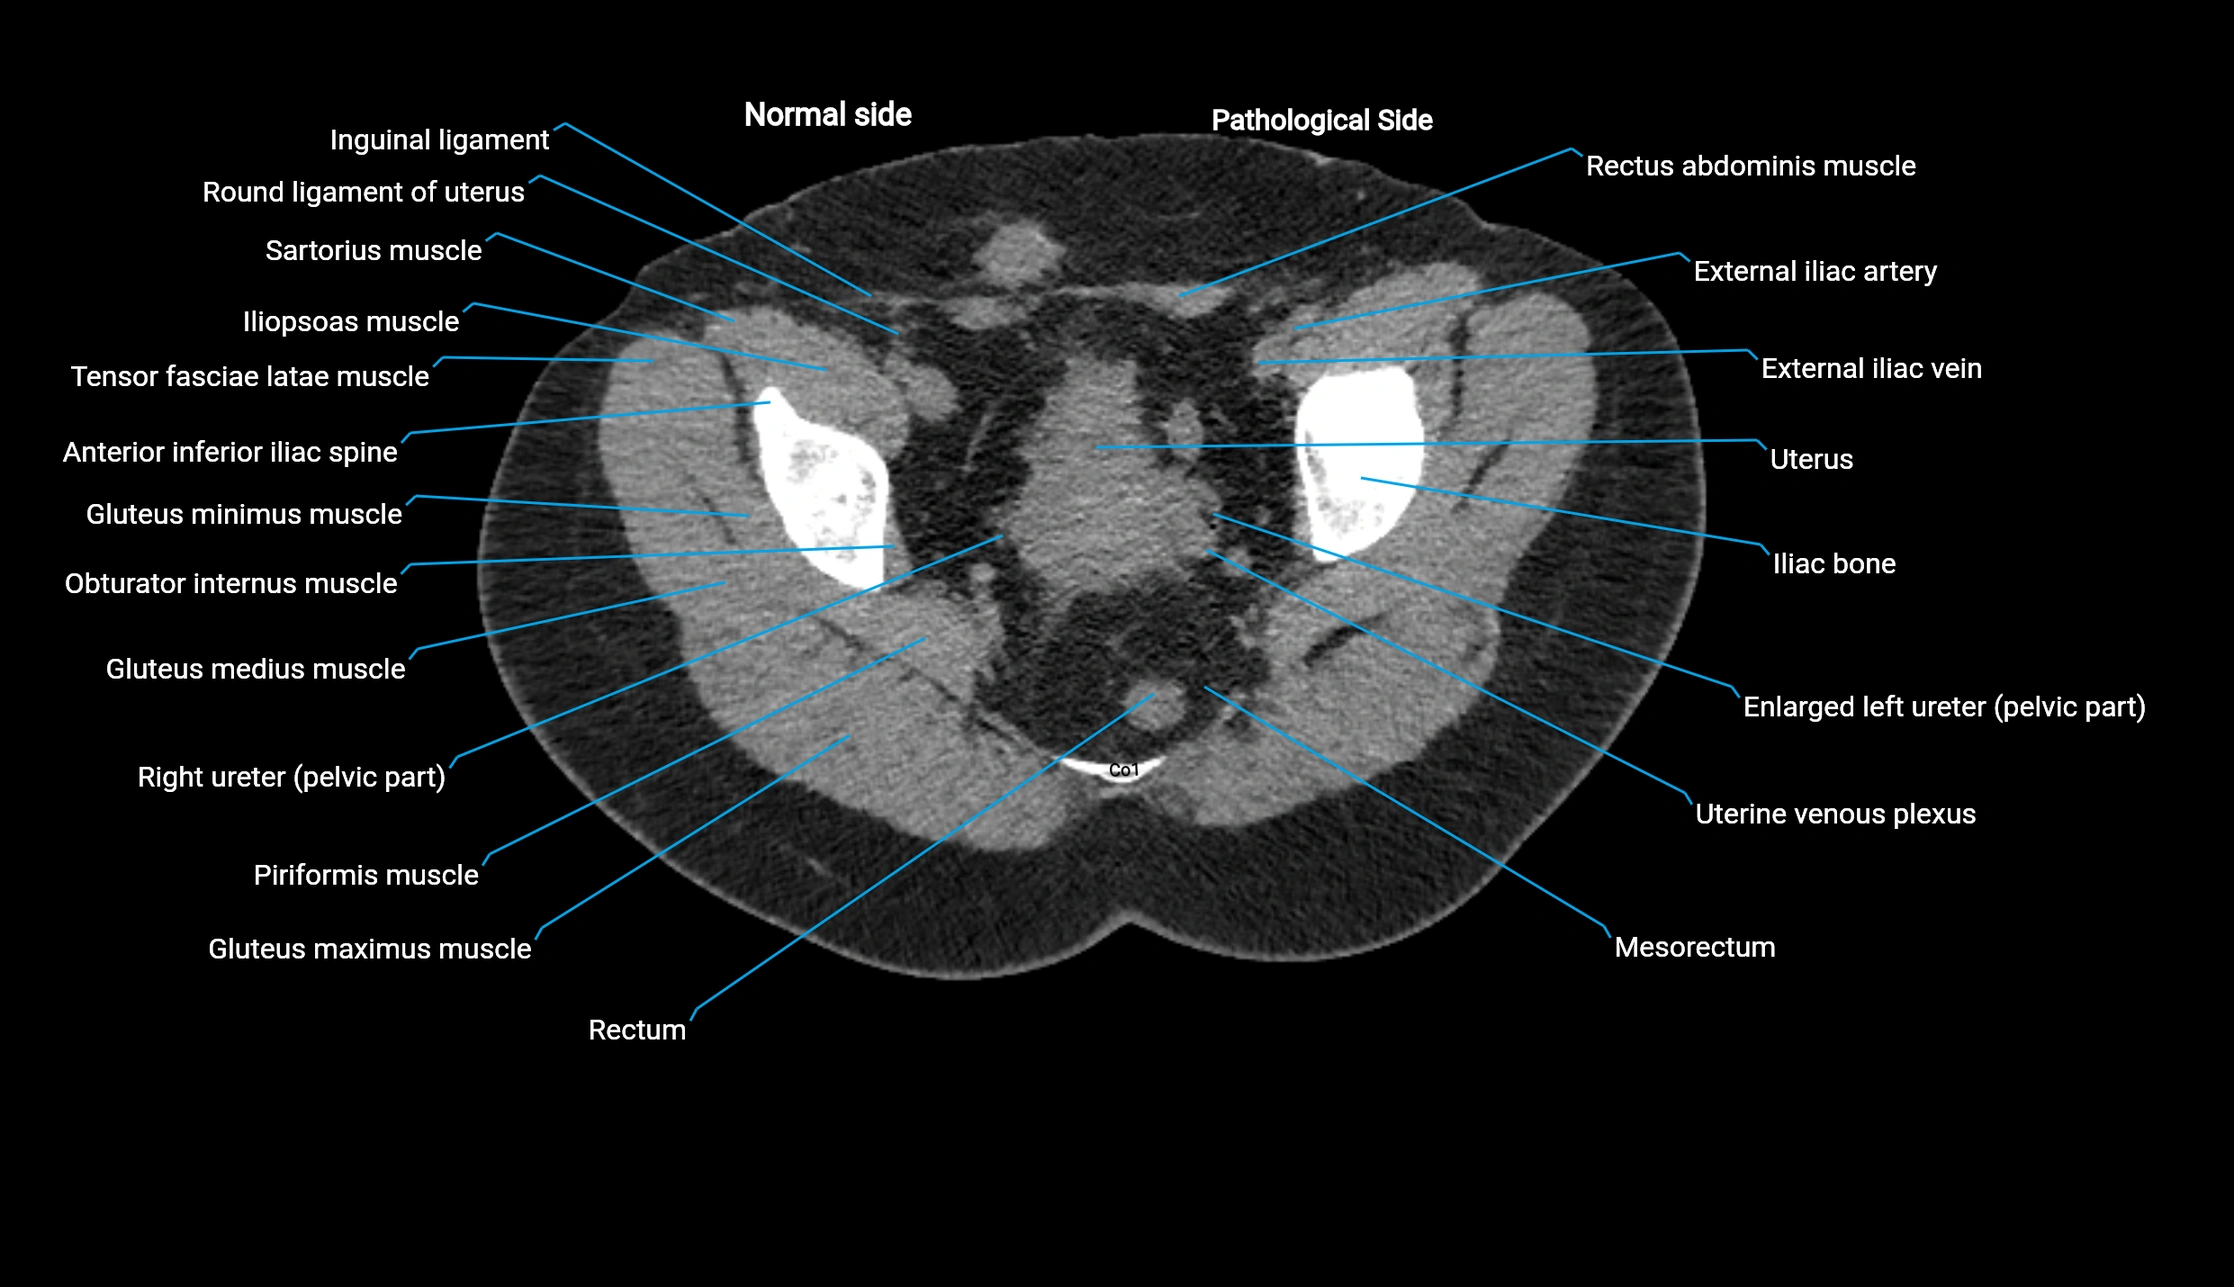

CT VRT 3D image

image